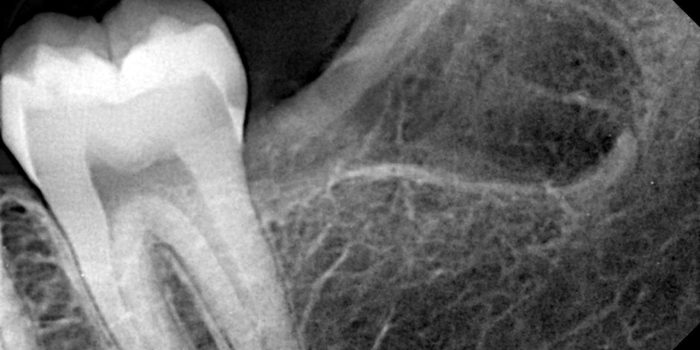

Need a clear and accurate diagnosis for your dental concerns? Our advanced tooth X-ray service in Karachi provides high-resolution digital imaging that helps detect cavities, infections, impacted teeth, bone loss, and hidden dental issues early and precisely.

Many dental issues develop beneath the surface and cannot be seen during a routine exam. Our state-of-the-art tooth X-ray services use high-definition digital radiography to accurately identify cavities, root infections, impacted teeth, periodontal bone loss, and other hidden oral conditions, allowing timely and effective treatment planning. At The Dental Clinic, we combine low-dose digital imaging with strict cross-infection control and international sterilization standards. Every dental radiograph is captured by experienced professionals to ensure optimal image clarity, minimal radiation exposure, and maximum patient safety.

Our advanced digital tooth X-rays deliver sharp, detailed images that help dentists identify problems early and plan treatments with confidence. Patients benefit from faster results and more accurate dental care decisions.

A tooth X-ray is a dental imaging technique that uses low radiation to capture detailed images of teeth, roots, and jawbone. It helps dentists identify cavities, infections, bone loss, and other issues not visible during a routine dental examination.

Dentists recommend tooth X-rays to detect hidden cavities, root infections, bone loss, impacted teeth, and other issues that are not visible during a routine oral examination.